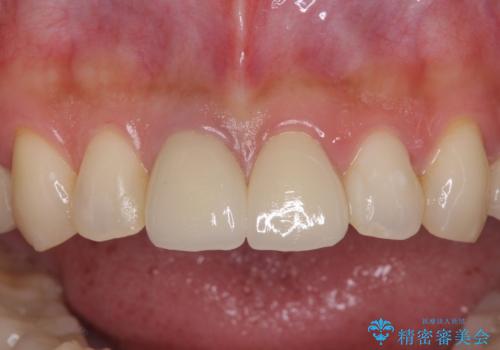

部分矯正を行った後にインプラント埋入と手前の歯の根管治療を行い、その後補綴治療を行うこととしました。

治療途中より、上の歯や反対側の銀歯、上顎前歯の色合いや下顎前歯のデコボコが気になってきたため、全てを治療することとしました。